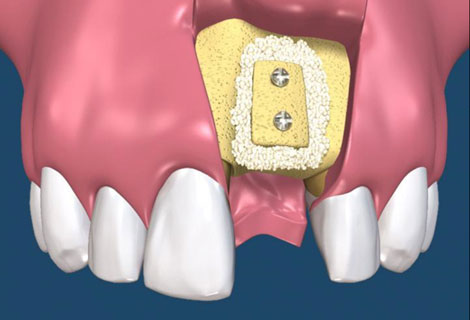

當我們遇到骨脊萎縮嚴重的區域(前、後牙區皆可能)時,可能會使用劈骨術(split technique)來增加骨脊的寬度,以便順利的植牙。而傳統劈骨術的做法技術需求性比較高,可以增加的骨脊寬度有限,而且如果骨脊因劈斷而有游離的情形時,那將損失更多得骨質。改良式的骨脊劈開術,可以得到較多與較可預測性的骨植增生,而且操作較為簡單(圖17-21)

圖17

圖18

圖19

圖20

圖21